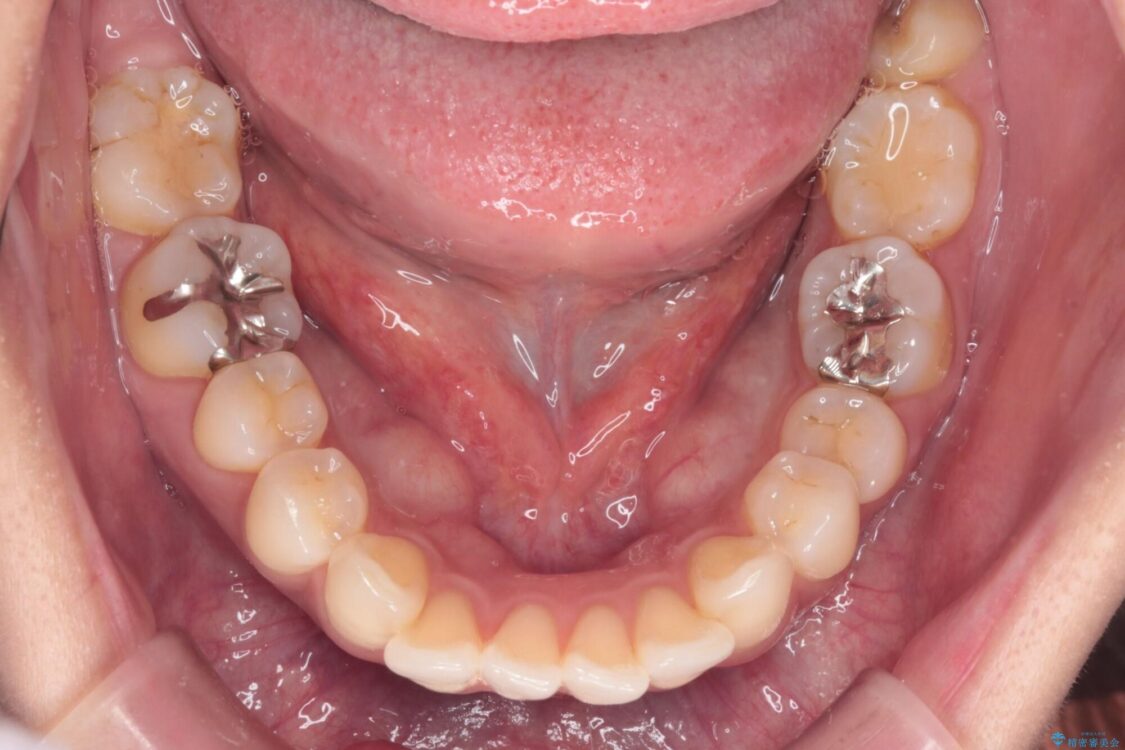

治療前

• 上顎前歯の突出を軽減 インビザラインによる抜歯矯正 治療前画像